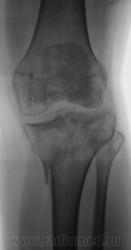

Консолидированый перелом проксимального эпифиза большеберцовой кости с повреждением наружного мениска и крестообразных связок ( вернее после их пластического восстановления ).

Александр Викторович,стояние отломков можно считать удовлетворительным?.+ вторичный ДОА+"пятнистый" остеопороз с участками остеосклероза.

стояние отломков, по истечении года, большого значения уже не имеет, главное что консолидация наступила, связочный аппарат восстановлен, в данном случаи нужно оценивать функцию, опорность, объем движений в данном суставе. Хотя внутренний мыщелок б\б кости просел прилично...